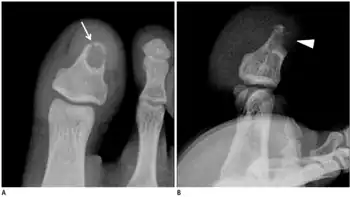

| a,b) Male with desmoplastic fibroma in first toe | |